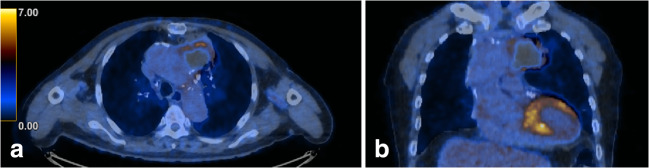

FDG PET/CT revealed heterogeneously increased FDG uptake along the periphery of the mass, with a maximum standardized uptake value (SUVmax) of 6.9 (Fig. 2). The majority of central portion of the mass was photopenic. Hematoma, rather than malignancy, was considered following the FDG PET/CT.

Fig. 2.

F-18 fluorodeoxyglucose (FDG) positron emission tomography/computed tomography (PET/CT) showed heterogeneously increased FDG uptake along the periphery of the mass; most of the central portion of the mass was photopenic